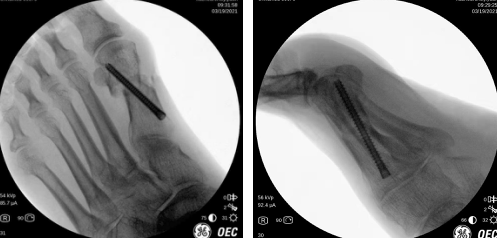

第二天,徐明亮主任周祥国医生团队为患者进行了微创踇外翻手术,手术仅花了30分钟就顺利完成。术中,手术医生切开0.8厘米小切口,采用低频超声骨刀清理骨赘,外移截骨,进行螺钉内固定,切口做了细致的美容缝合,几乎看不到。

术中,矫形后螺钉内固定